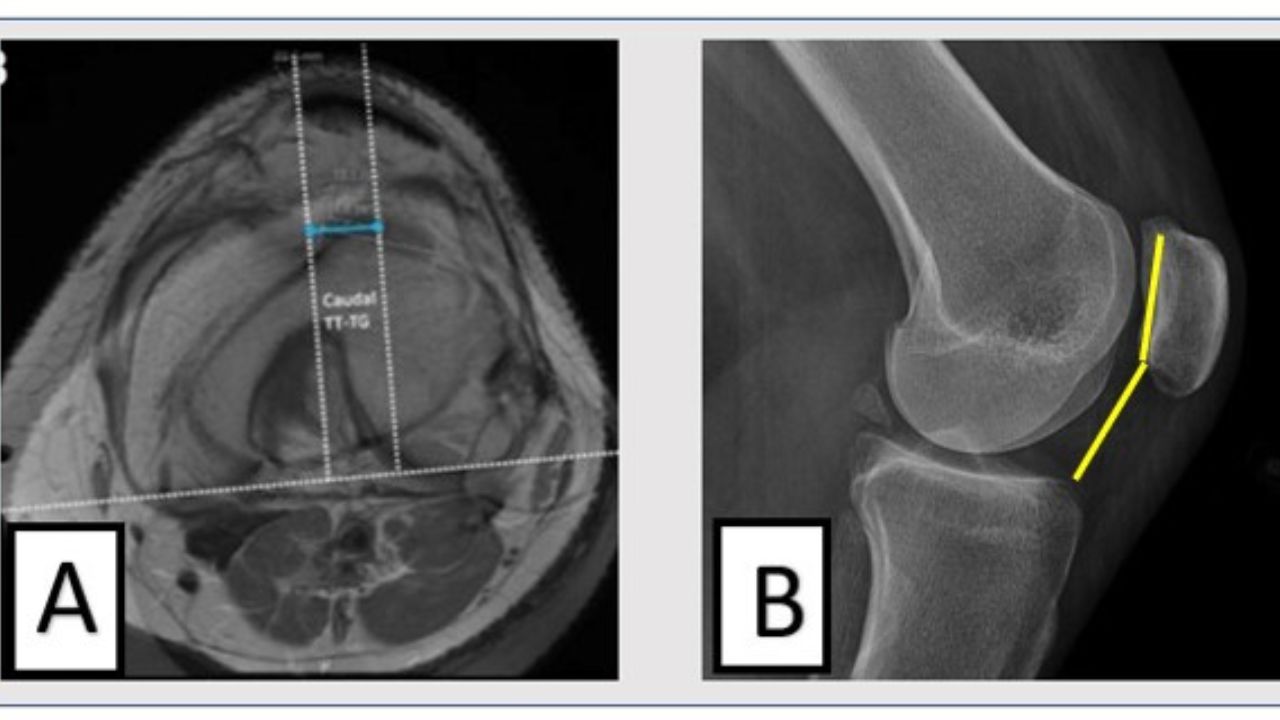

O diagnóstico é feito no pronto-socorro através de exames físicos e de imagem, como o raio-x, para confirmar o deslocamento (caso ele ainda exista) e verificar se há fraturas associadas. Após a redução, uma ressonância magnética é fundamental para avaliar a extensão total dos danos, principalmente para checar a situação do ligamento patelofemoral medial e se há lesões na cartilagem. Esses achados são cruciais para definir o plano de tratamento e evitar que o problema se torne recorrente.